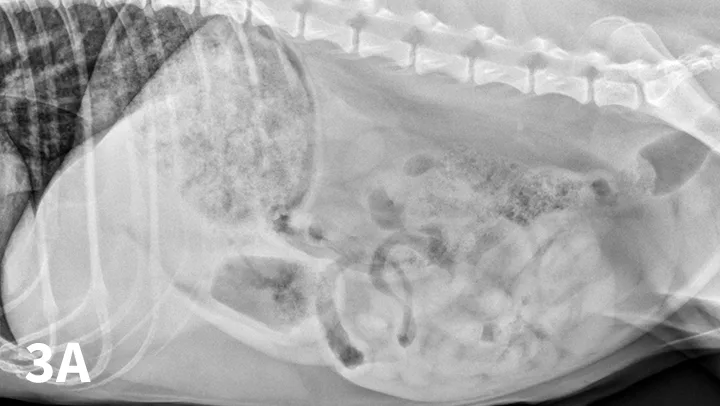

FIGURE 3A

Left lateral radiograph of a 4-year-old crossbreed dog with a history of vomiting. The patient was clinically stable. Granular, well-defined soft tissue opaque material is present within the fundus of the stomach, consistent with food or foreign material.

2. Repeat Abdominal Radiography 24 to 36 Hours After Fasting

Food or ingesta can look similar to foreign material and can be difficult to differentiate. Depending on the presentation, radiography can be repeated after fasting period to document passage (or lack thereof) of GI content (Figures 3 and 4). Persistence of opaque foreign material in the same location over a 24- to 48-hour period should increase the suspicion of partial obstruction. In cases of complete mechanical obstruction, radiographic features of obstruction can develop during this time. This makes it easier to recognize the obstruction radiographically (Figure 4C).